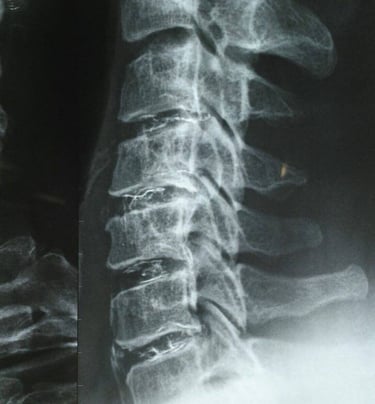

This sterile implantable medical device is based on jellified ethanol in which

an opaque agent in X-rays, the tungsten was added.

To determine the impact of ethanol gel chemonucleolysis (EGCh) on the radiological picture of the treated intervertebral disc...

The results showed a decrease in the size of the protrusion and GI zone in the treated intervertebral disc. The presence of a high-intensity zone (HIZ) on baseline magnetic resonance imaging was found to be a good predictor of the timing and outcome of treatment, and an increase in disc height was observed in adjacent segments.